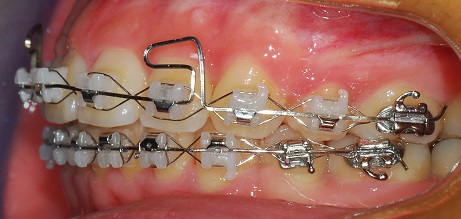

이래서 이번달에 무시무시한 다리같은걸 위 와이어에 장착했습니다

그 철사는 윗 니들을 들어올리는 역할을 한다구 해요

그리고 그 철사에 고무줄을 걸기로 했습니다. 이번엔 잘 걸어야 겠어요ㅎㅎㅎㅎ

측면 사진

예전에는 윗니와 아랫니를 다물었을 때 공간이 있었는데 지금은 아예 없어졌어요~